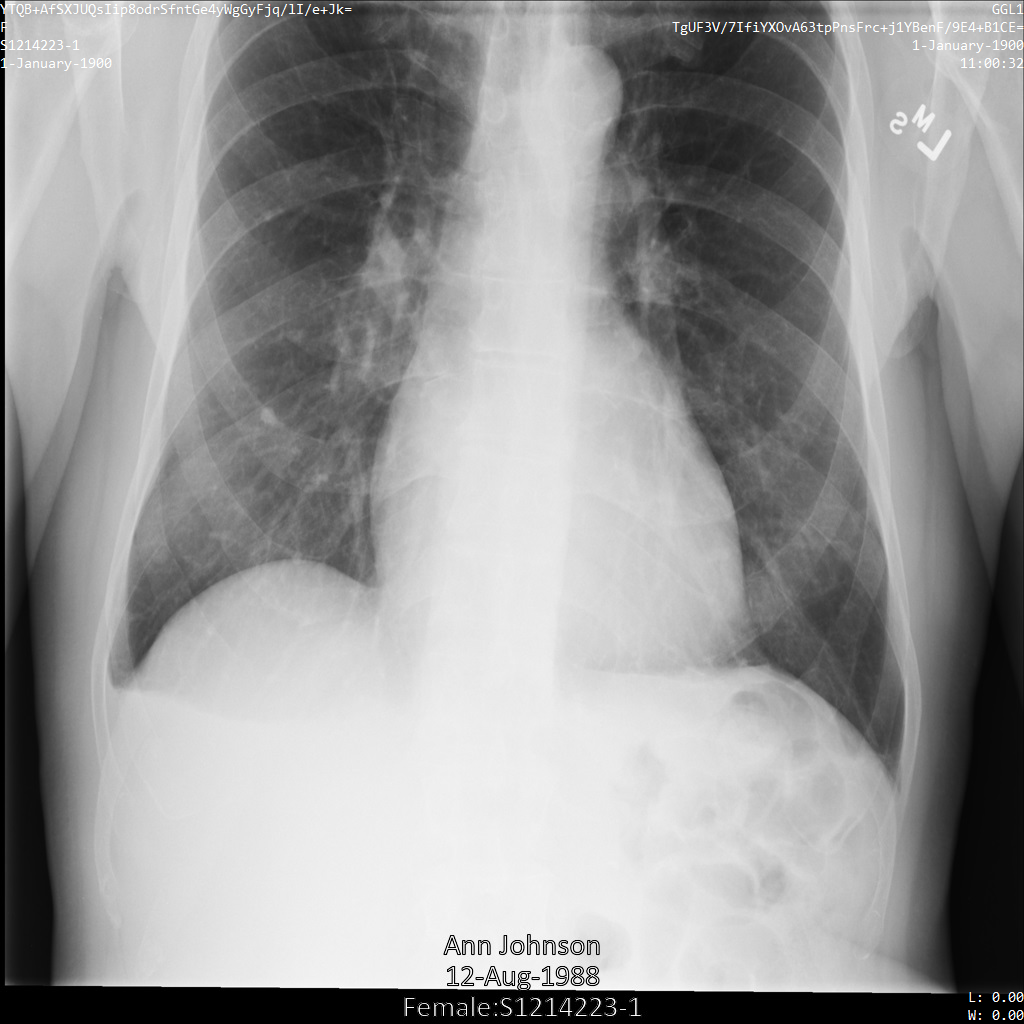

将图片提交到 Cloud Healthcare API 后,图片显示如下。除了 removelist 中提供的标记之外,便只有 PatientBirthDate 会从图片中移除,因为它是 removelist 中唯一与图片中可见的元数据对应的标记。

虽然图片顶部角落的 PatientBirthDate 已根据 removelist 中的配置进行了遮盖,但图片底部的烧屏 PHI 仍会保留。如需一并移除烧屏文字,请参阅遮盖图片中的烧屏文字

dicom_removelist